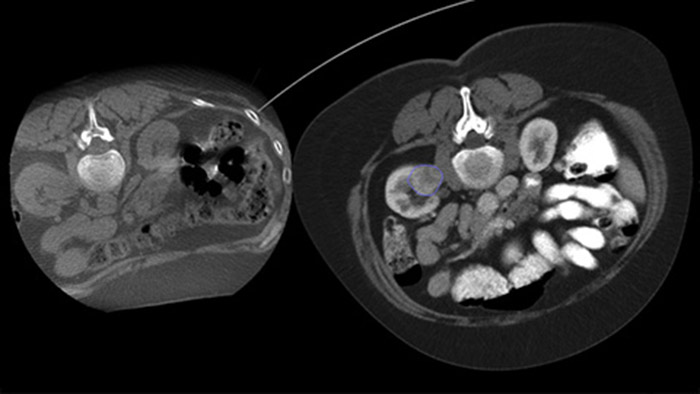

La ablación percutánea (radiofrecuencia, microondas y crioablación) es un tratamiento mínimamente invasivo de eficacia comprobada de tumores renales, hepáticos, pulmonares y óseos. Es fundamental definir los límites del tumor y decidir un número óptimo de agujas y la trayectoria de la aguja correspondiente para poder realizar un tratamiento tumoral completo y no causar daños en el tejido circundante. Navegar con precisión en dosis bajas hacia la lesión de interés sin necesidad de cambiar la posición de la aguja aumenta la oportunidad de éxito y reduce el riesgo de complicaciones en las biopsias o ablaciones. La confirmación del criterio de valoración del tratamiento de ablación se puede lograr con imágenes 3D mientras el paciente aún se encuentra en la mesa.

Con CBCT, adquiera una CBCT posterior a la ablación para demostrar el alcance de la cobertura del tumor y confirmar la integridad de su tratamiento.

SmartCT Soft Tissue ofrece una técnica de adquisición de CT de haz cónico (CBCT) aumentada con guía paso a paso, visualización 3D avanzada y herramientas de medición; todas en el módulo de pantalla táctil de la mesa.